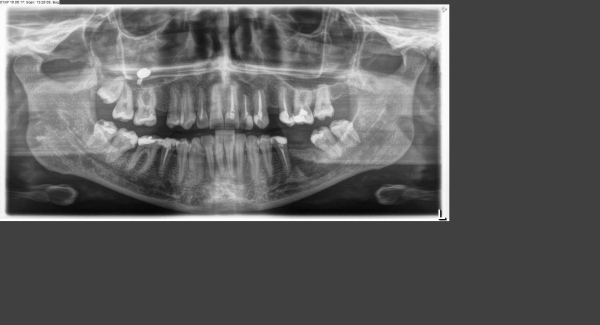

На снимке в области 7-го верхнего левого зуба (2.7) костная ткань не имеет изменений. Насколько позволяет качество снимка оценить ситуацию, верхушка корня/корней 2.7 зуба находится в верхнечелюстной пазухе. При таком анатомическом строении, любые воспалительные процессы у верхушки корня данного зуба будут провоцировать воспаление верхнечелюстной пазухи — одонтогенный гайморит, о чем могут свидетельствовать такие жалобы, как чувство распирания в области верхней челюсти, лба, иррадиация боли к уху и др.

Кроме того, возможной причиной Ваших жалоб может являться 6-й зуб на этой же стороне.

В проекции правой верхнечелюстной пазухи отмечается участок просветления, возможно, это просто дефект снимка.